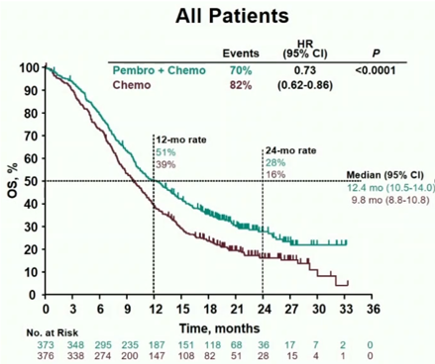

2020年6月19日,我国国家药品监督管理局批准帕博利珠单抗(国内俗称为“K药”)和卡瑞利珠单抗这两个PD-1免疫检查点抑制剂用于二线治疗局部晚期或转移性食管鳞癌...

晚期食管癌预后较差,延长生存期迫在眉睫据世界卫生组织一项最新统计的全球癌症发病率数据显示,2018年有57.2万人新诊断为食管癌,同时又有50.9万人死于食管癌,...

2020年的金秋,欧洲肿瘤内科学会(ESMO)年会如期而至,免疫治疗在消化系统肿瘤的治疗中大放异彩。其中食管癌领域最重磅级研究——Keynote-590研究在...